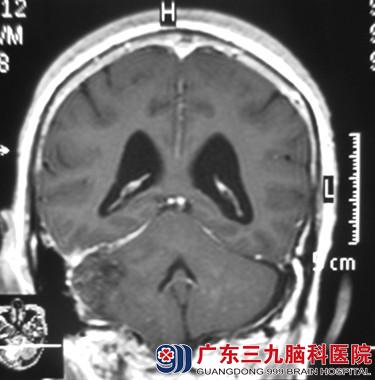

经头颅MR检查提示后颅窝右侧占位性病变,大小约55.3*44.8*41.8mm,考虑脑膜瘤可能性大。完善相关检查后,由鲁明主任主刀,在全麻下行右侧后颅窝横窦、小脑幕下脑膜瘤切除术,术中显微镜下见硬膜下肿瘤组织,鲜红色、质软、血供丰富,与小脑幕粘连,边界清楚,沿肿瘤基底分离,见肿瘤长入横窦,分块切除肿瘤,肿瘤全切,手术顺利结束。术后经过专科治疗护理,李大姐康复出院。术后病理结果:过渡型脑膜瘤(WHO I级)。